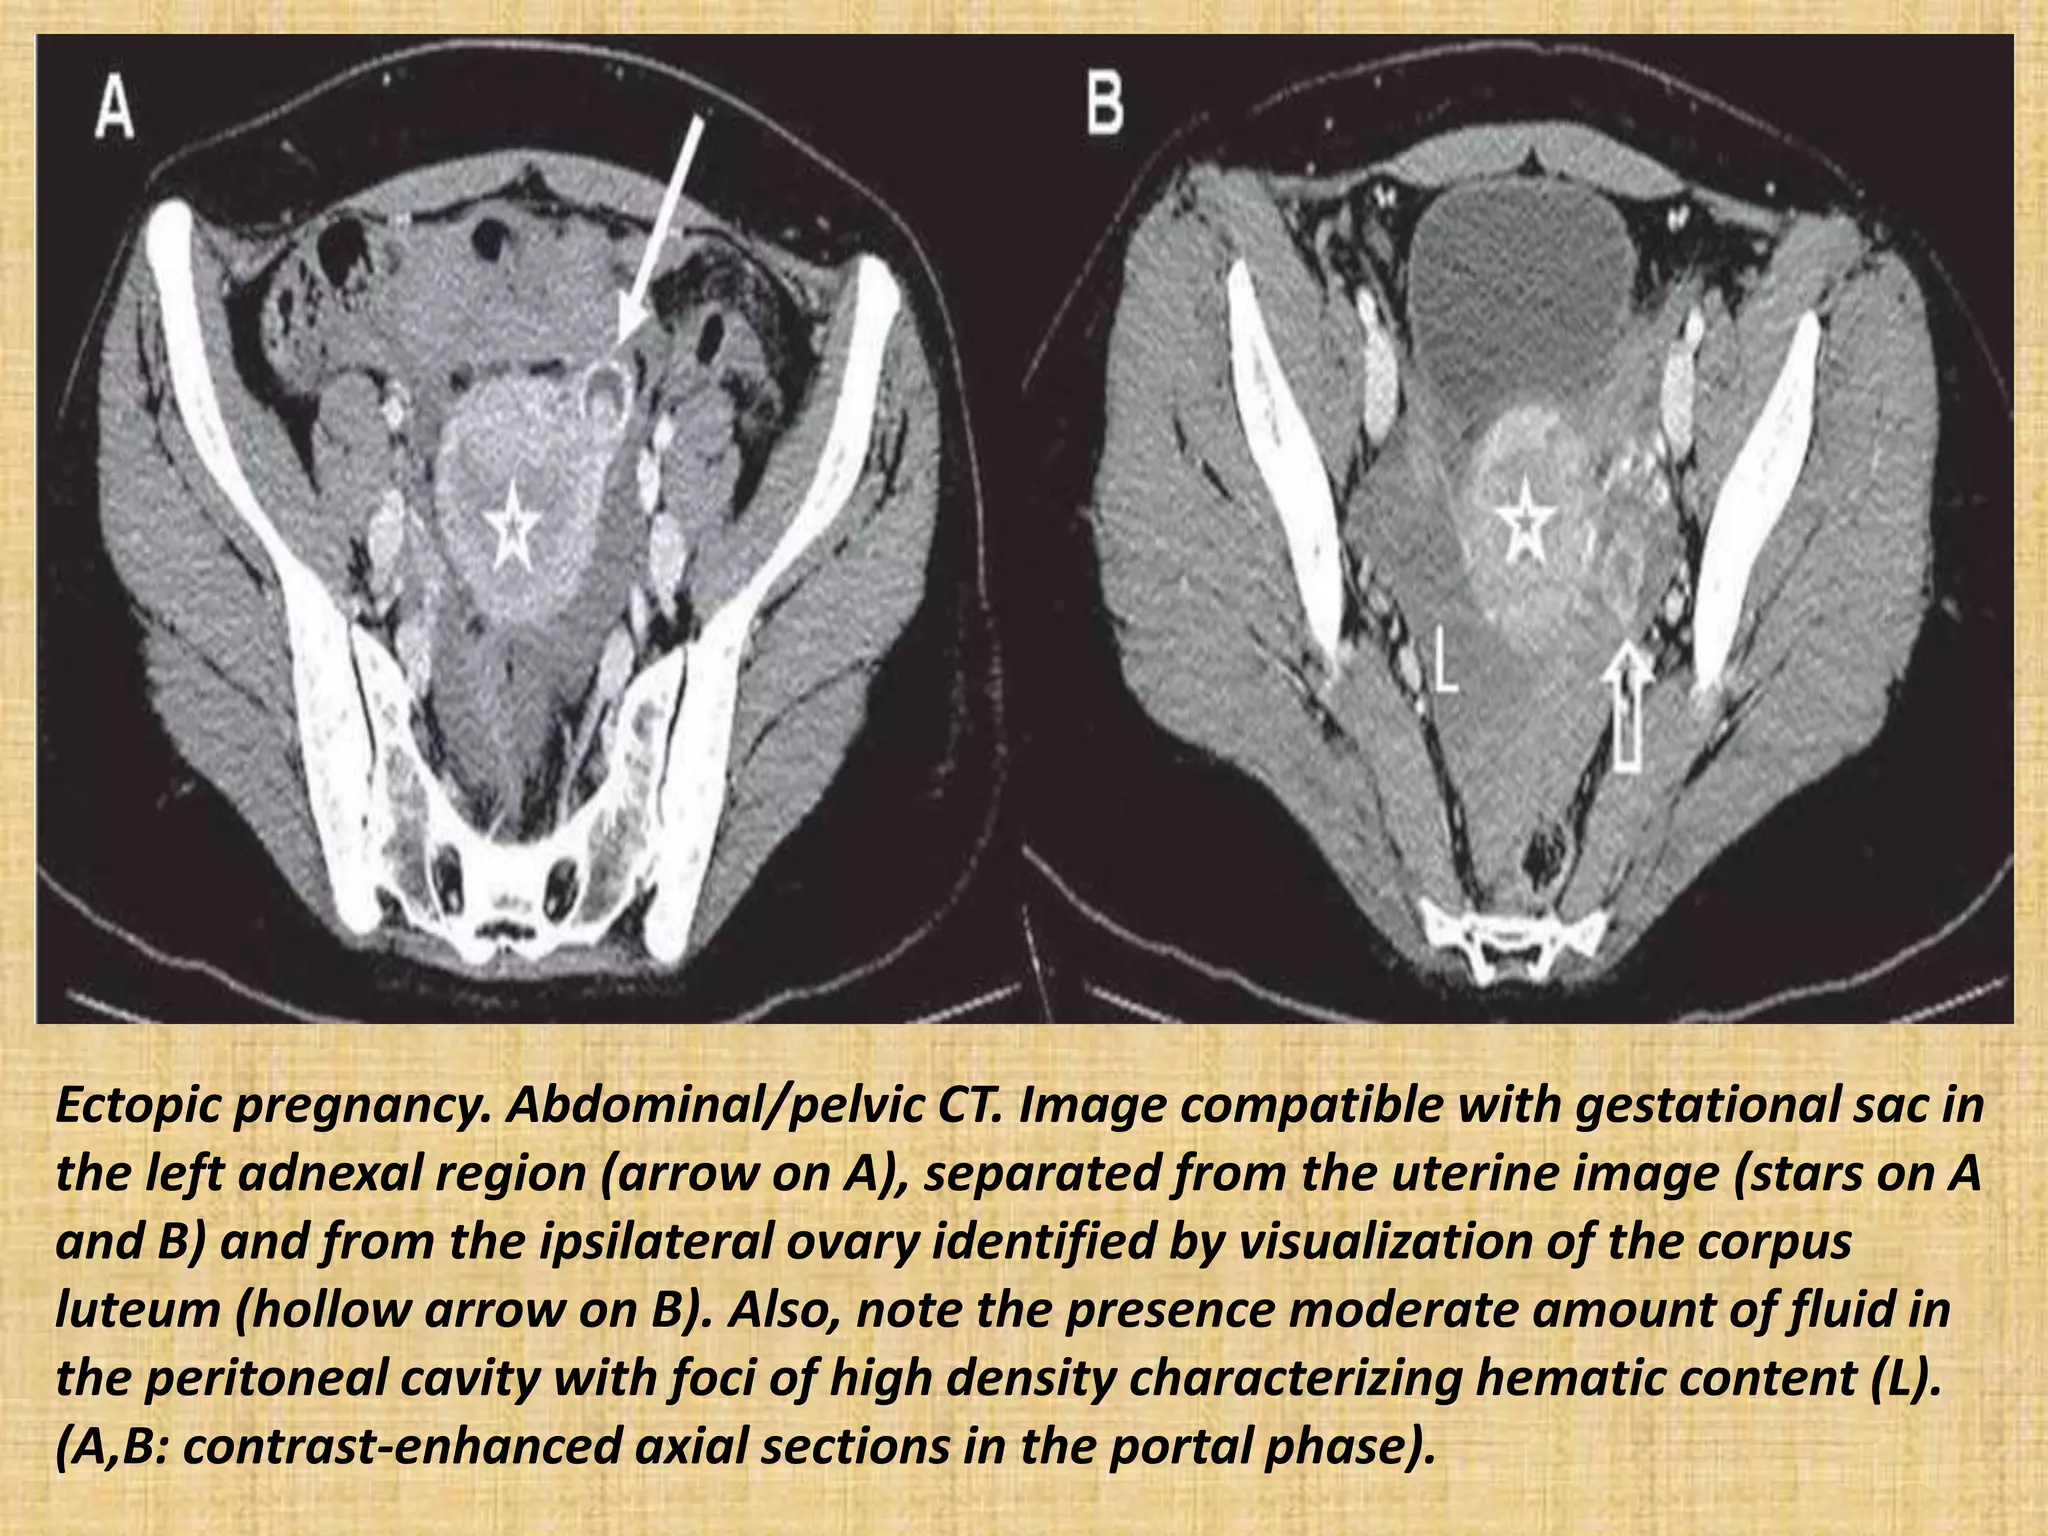

Ectopic pregnancy. Abdominal/pelvic CT. Image compatible with gestational sac in

the left adnexal region (arrow on A), separated from the uterine image (stars on A

and B) and from the ipsilateral ovary identified by visualization of the corpus

luteum (hollow arrow on B). Also, note the presence moderate amount of fluid in

the peritoneal cavity with foci of high density characterizing hematic content (L).

(A,B: contrast-enhanced axial sections in the portal phase).

Ectopic pregnancy. Abdominal/pelvicCT. Image compatible with gestational sac in the left adnexal region (arrow on A), separated from the uterine image (stars on A and B) and from the ipsilateral ovary identified by visualization of the corpus luteum (hollow arrow on B). Also, note the presence moderate amount of fluid in the peritoneal cavity with foci of high density characterizing hematic content (L). (A,B: contrast-enhanced axial sections in the portal phase).